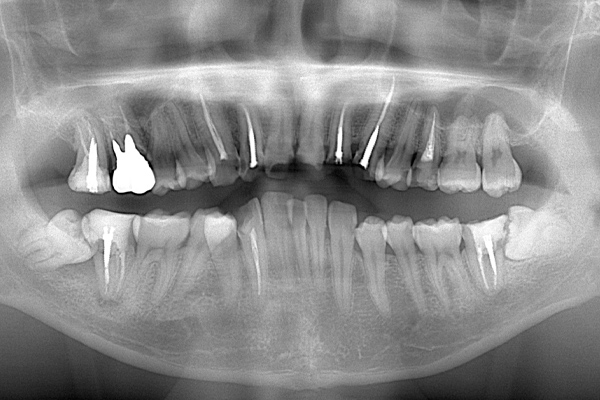

こちらは、下顎の親知らずが半埋伏で斜めにはえています。また、前の歯との間に虫歯をつくってしまっていたり、前の歯の根の先端の方まで骨が溶けてしまっています(智歯周囲炎)。

このように他の残さないといけない歯に悪影響を与えている親知らずに関してはなるべく早めに抜いたほうがよいです。